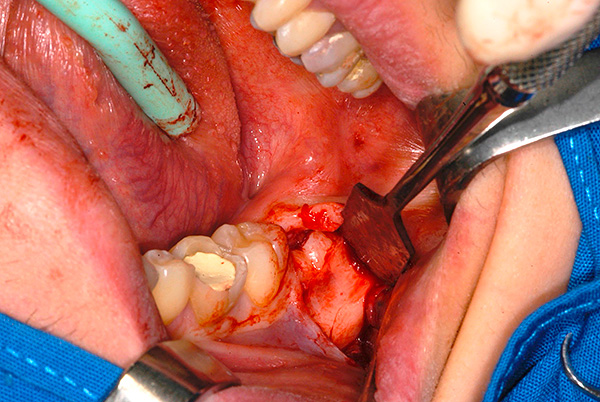

Foto di un dente semi-artificiale di saggezza: